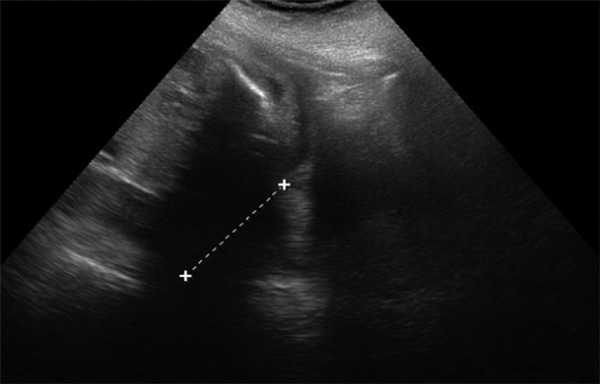

Челюстной индекс рассчитывался после измерения переднезаднего диаметра нижней челюсти плода в осевой плоскости в соотношении с бипариетальным размером (рис. 7). Данный индекс не зависел от срока гестации.

Рис. 7. Переднезадний диаметр нижней челюсти плода / Fig. 7. Anteroposterior diameter of the lower jaw of the fetus